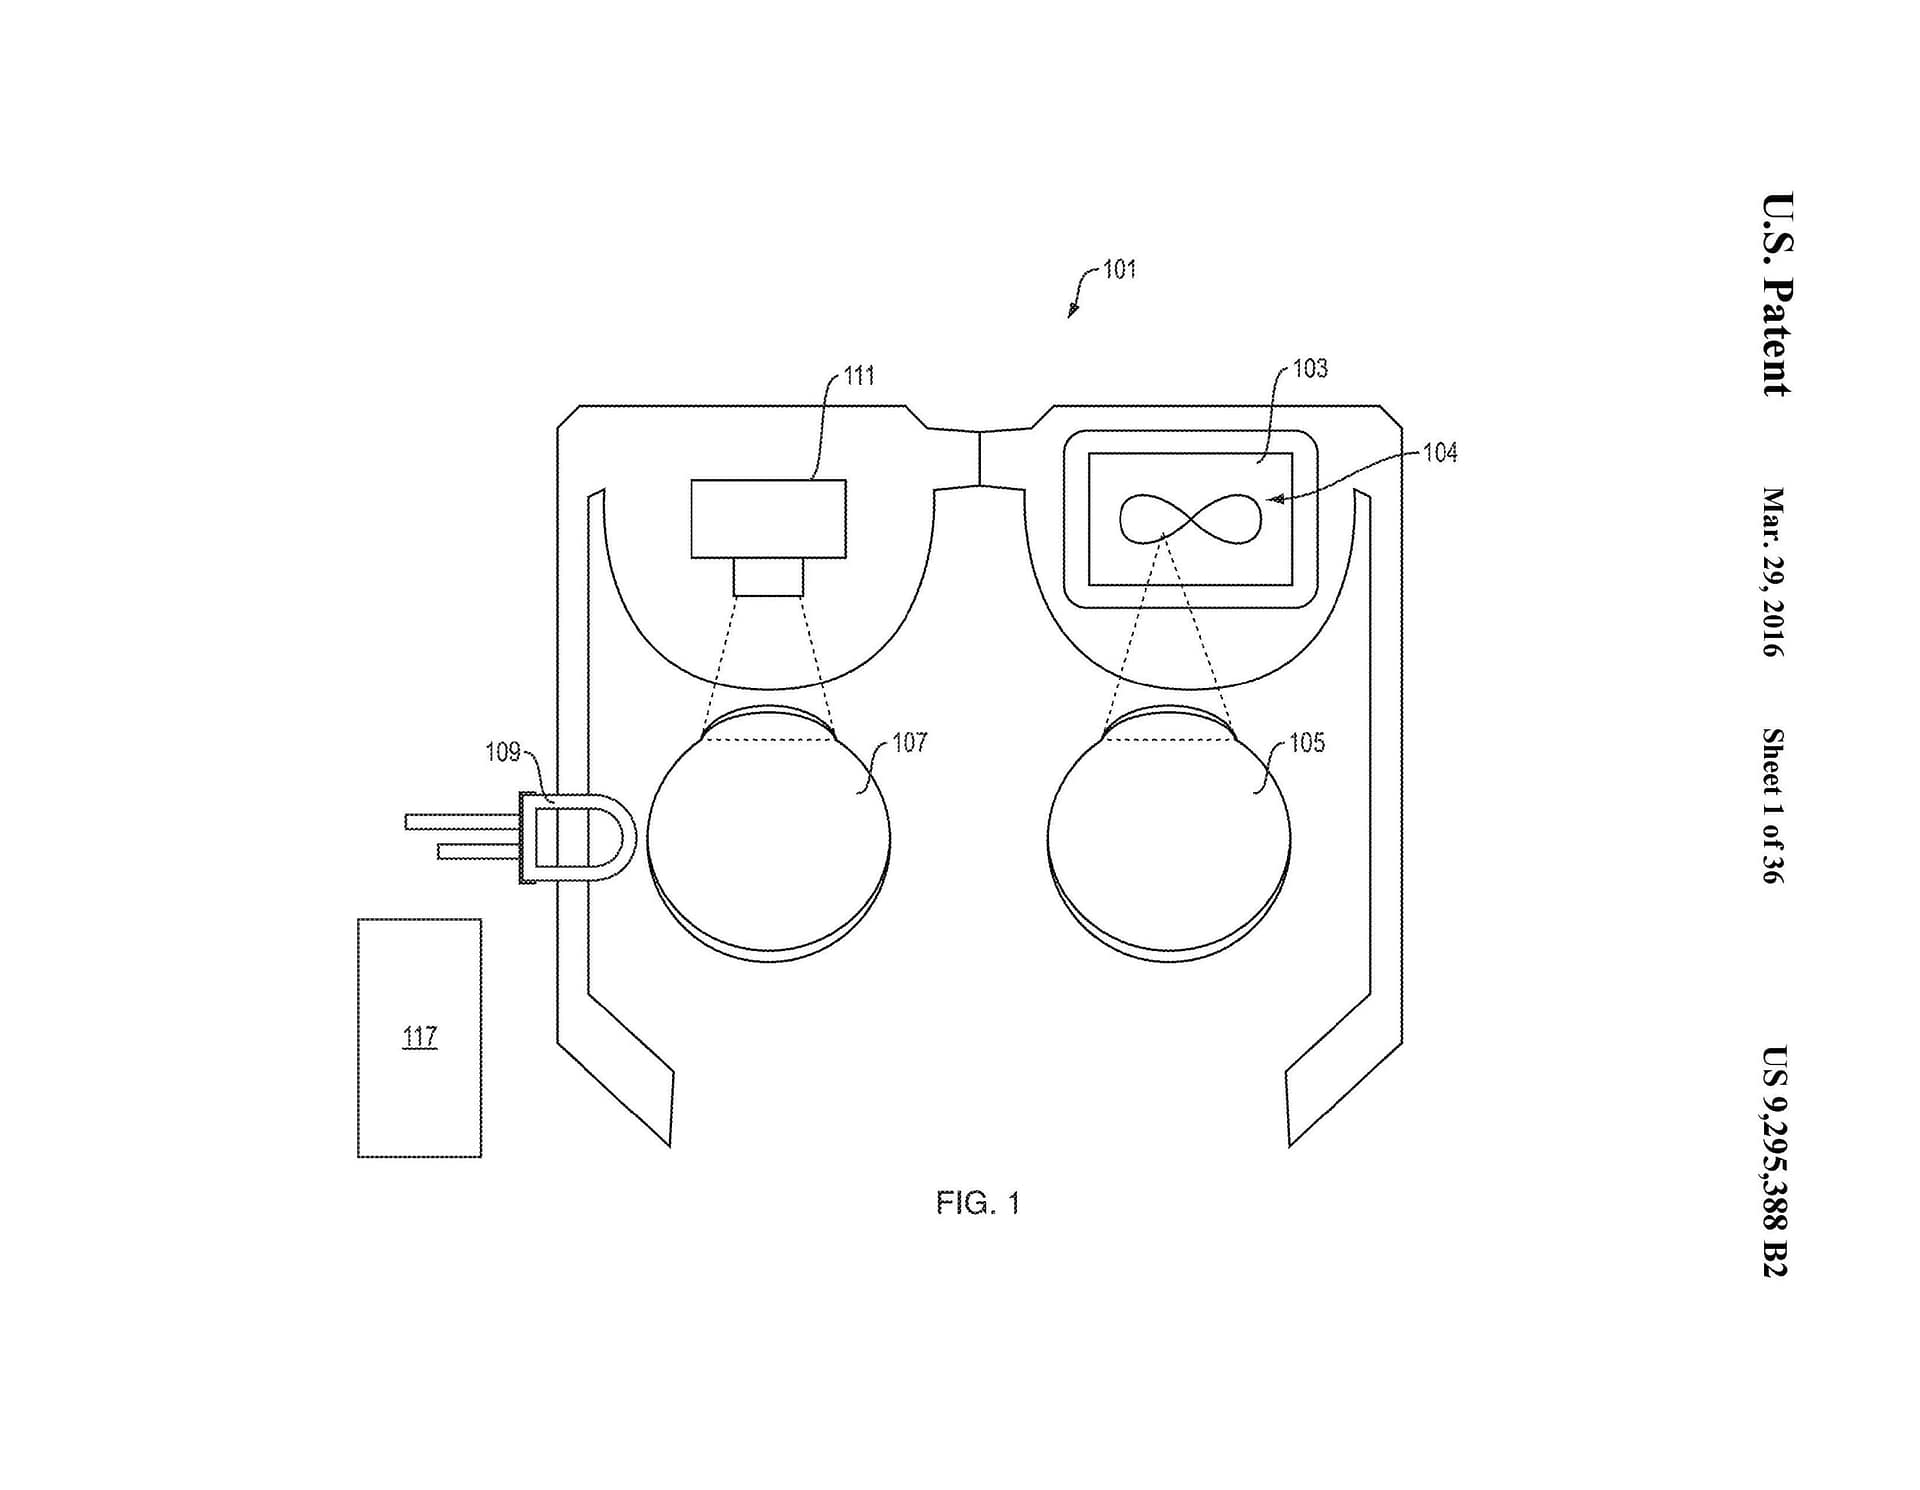

This invention comprises an apparatus for retinal self-imaging. Visual stimuli help the user self-align his eye with a camera. Bi-ocular coupling induces the test eye to rotate into different positions. As the test eye rotates, a video is captured of different areas of the retina. Computational photography methods process this video into a mosaiced image of a large area of the retina. An LED is pressed against the skin near the eye, to provide indirect, diffuse illumination of the retina. The camera has a wide field of view and can image part of the retina even when the eye is off-axis (when the eye’s pupillary axis and cameras optical axis are not aligned). Alternately, the retina is illuminated directly through the pupil, and different parts of a large lens are used to image different parts of the retina. Alternately, a plenoptic camera is used for retinal imaging.

In an initial alignment step, the imaging device displays real-time visual feedback to one eye (the stimulus eye) of a user. The visual feedback is indicative of (i) the pupillary axis of the user’s eye that is being imaged (the test eye) and (ii) the optical axis of the device’s camera. For example, an LCD in the device may display visual feedback that comprises a circle representative of the optic disc of the test eye (which serves as an approximate indication of the pupillary axis) and a square indicative of the center of the camera (which serves as an approximate indication of the optical axis of the camera). This real-time visual feedback guides the user as the user changes direction of gaze in order to self-align the two axes. Once the two axes are aligned, the imaging device displays a video of moving visual stimuli to the stimulus eye. The user’s stimulus eye tracks this moving stimuli.

Due to bi-ocular coupling, the test eye moves (rotates) in a similar path. As the test eye rotates into different positions, a camera in the device captures multiple images of different portions of the retina of the test eye. Each of these images may capture only a small portion of the retina. These images are processed and stitched together to form an image of a large area of the retina. This large field of view (FOV) image of the retina can be displayed to the user in real-time. As the test eye rotates (while bi-ocularly coupled to the stimulus eye), the test eye moves into many rotational positions in which the test eye is “off-axis’ with respect to the camera. As used herein: (i) an eye is “off-axis’ with respect to a camera if the optical axis of the camera is not pointed at the pupil of the eye; and (ii) an eye is “on-axis’ with respect to a camera if the optical axis of the camera is pointed at the pupil of the eye. The camera has a wide FOV and thus can capture an image of at least a small part of the retina, even when the test eye is off-axis.